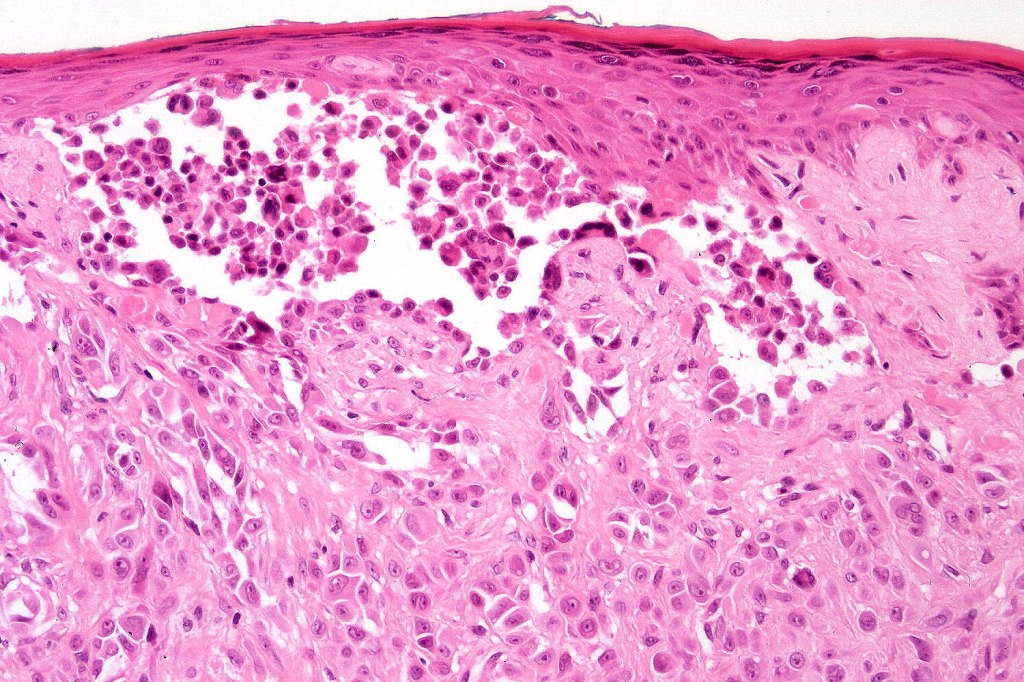

•Junctional nests often vertically orientated, dyscohesive with a surrounding retraction artifact

•Pleomorphism is almost invariable but affects all of the population to the same extent i.e., the cells & nuclei all look very much the same

•Kamino bodies (often multiple) are a characteristic feature

•Lymphocytic infiltration at the base of the lesion